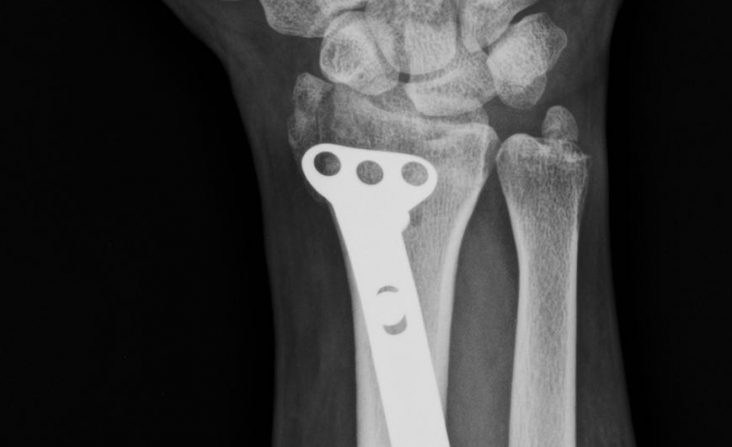

Dr Kamran Saeed is a well known and extremely experienced orthopedic and trauma surgeon of Lahore, Pakistan .